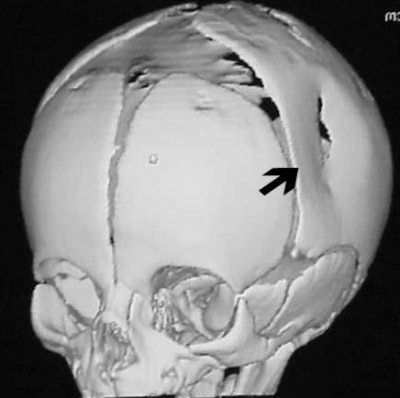

Three-dimensional reconstructed images in surface-shaded volume rendering show an obvious breech of the skull in the affected area (figures CT 7 and CT 8). Detectives matched the defect to a pair of the father’s cowboy boots. He was charged and convicted of beating his wife during the pregnancy.

![]() |

| Figure CT 8 |